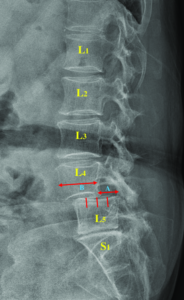

Най-често спондилолистезата се наблюдава в лумбалния отдел на гръбначния стълб, особено между прешлените L4–L5 и L5–S1. При това състояние стабилността на гръбначния сегмент може да бъде нарушена, което може да доведе до болка в кръста, ограничена подвижност или симптоми, които се разпространяват към краката.

Как изглежда спондилолистезата на образно изследване

Спондилолистезата най-често се установява чрез образни изследвания като рентгенография или MRI. Тези изследвания позволяват да се види позицията на прешлените и дали има приплъзване между тях.

На рентген или MRI може да се наблюдава:

приплъзване на един прешлен спрямо друг

промени в междупрешленния диск

стеснение на пространството около нервните структури

дегенеративни промени в ставите на гръбначния стълб

Образните изследвания дават важна информация за структурата на гръбначния стълб, но винаги трябва да се интерпретират заедно със симптомите на пациента.